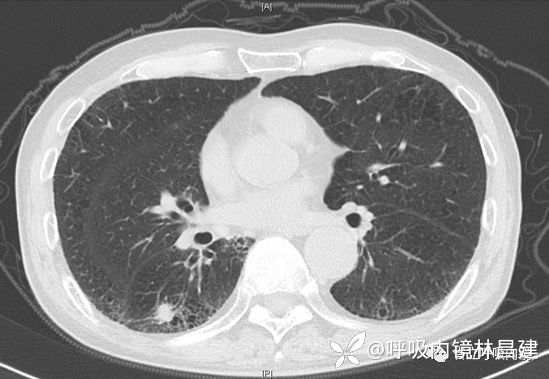

作为一名呼吸科医生,经常有病人拿着一张胸部CT找你,医生帮我看下片,比如下图。病人最关心的是这个结节病灶是良性还是恶性,开还是不开。但是单纯看片子,你是不能下结论的。这个时候你就能发挥专科的优势,做个气管镜吧。

再回来看这张图,其实这张图上包含很多信息,这个层面右肺的三个叶都呈现了,斜裂及水平裂都有,但是支气管树的管腔只有中叶和下叶,片上的病灶位于下叶,下叶最早出现的就是背段。经过CT的精准定位(你需要看薄层CT,最薄的那种,来来回回地翻看),我们知道结节可能位于右下叶背段b亚段,知道这个非常重要。